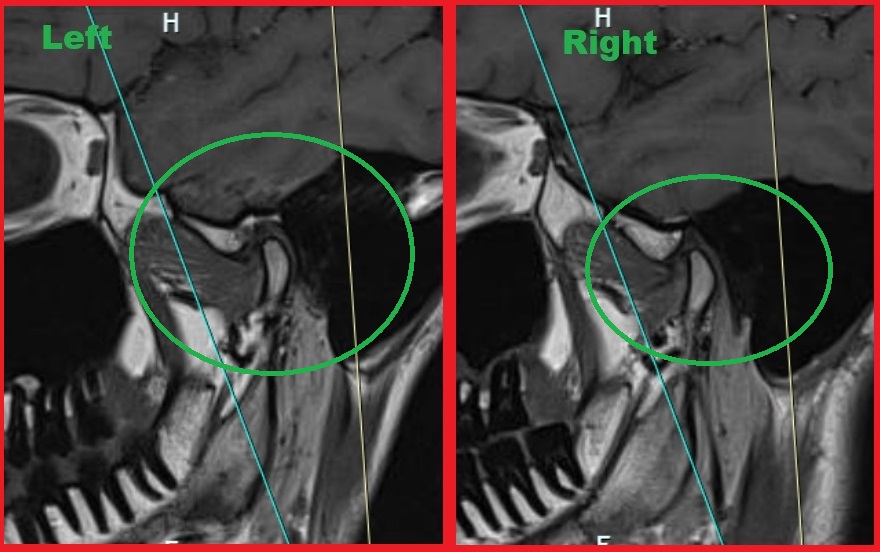

Я в разрезе у себя МРТ заметил что с одной стороны мыщелок кости какой-то более острый, стертый будто. Почему мне никто об этом не сказал, хотя и КТ делал и репорт МРТ получал, никто об этом там даже не написал. Я что-то не понимаю?

Я ещё несколько снимков в разрезе склеил и загрузил и чатгпт 4. И вот что он сказал. Пикрелейтед 1 и 2 снимки с закрытым и открытым ртом. Пикрелейтед 3 анализ чатгпт на основе снимка 1 (2ой ещё не загрузил ему потому что лимит на сегодня загрузок). Теперь вопрос. Если я чат ГПТ видит воспаление, неровность, то почему мой радиологист нихуя этого не увидел?